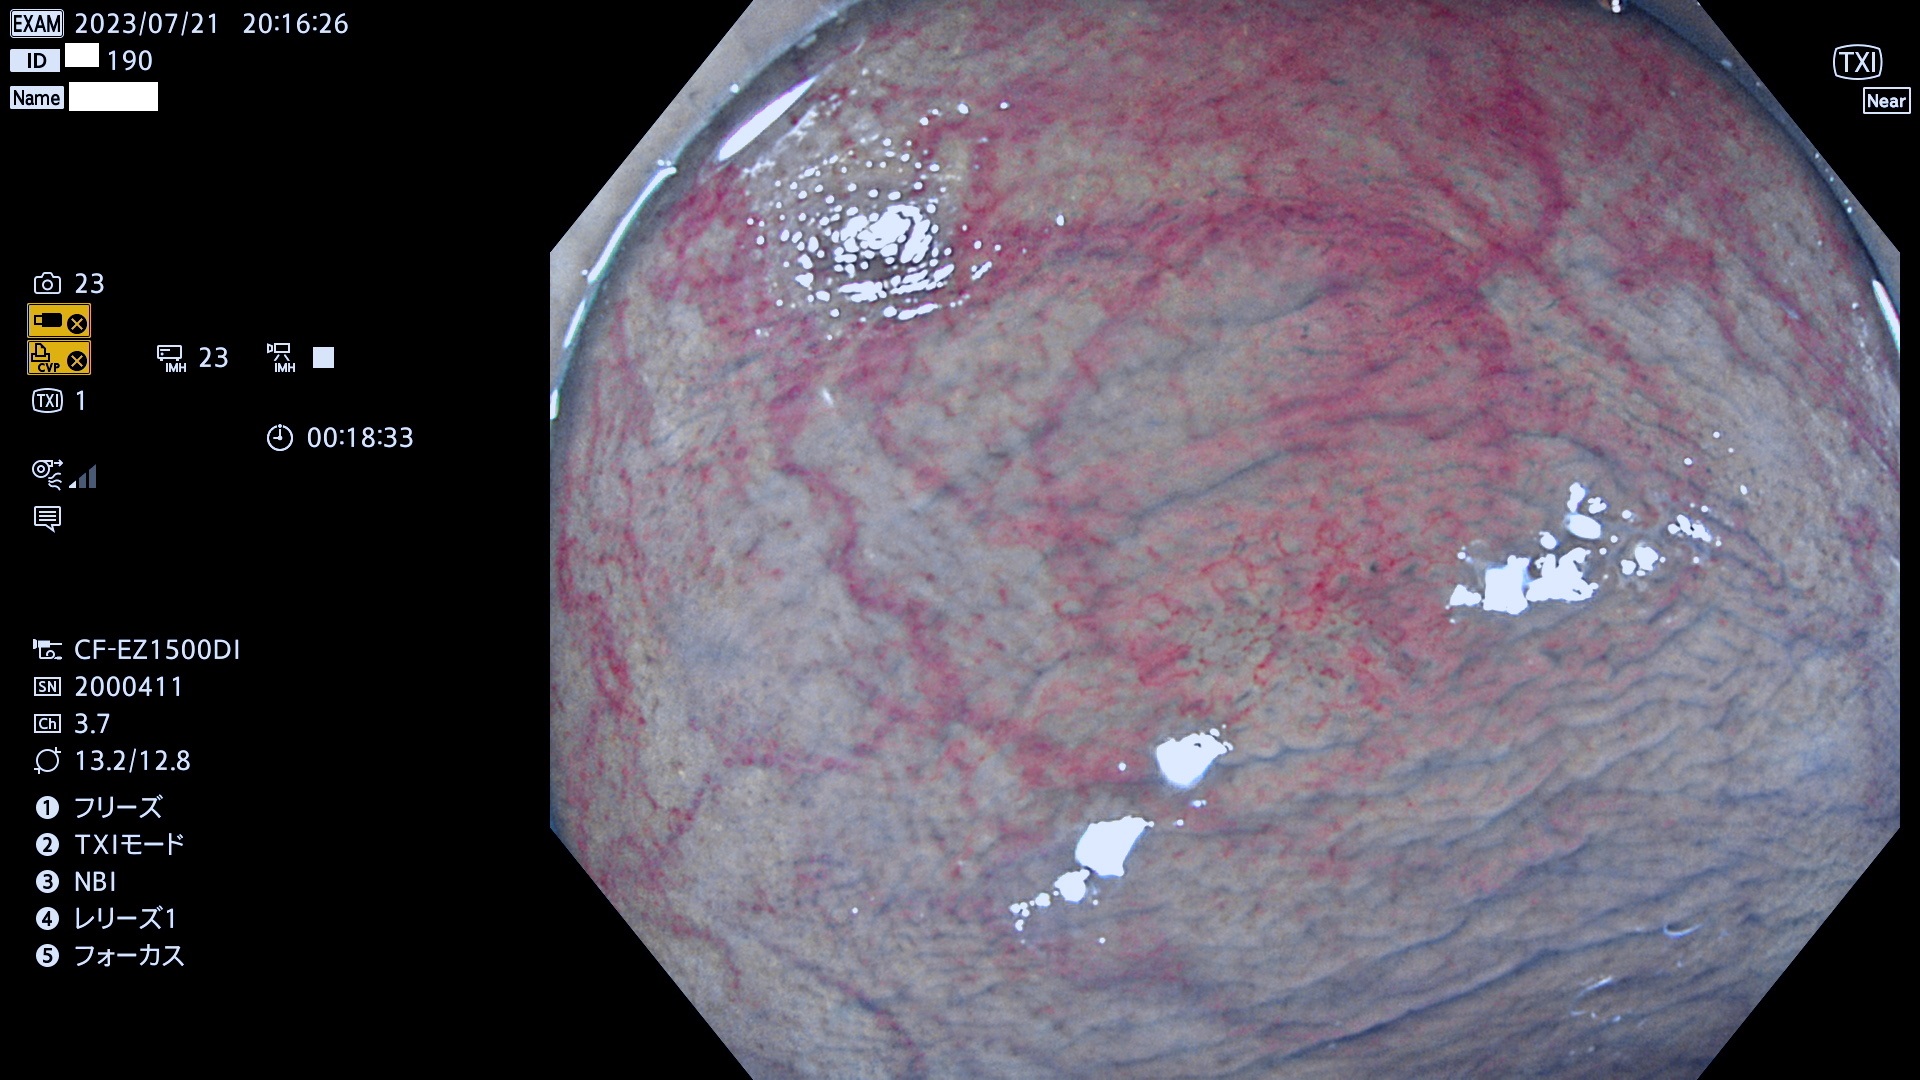

「表面型腺腫(Flat Adenoma)の中で、完全に平坦な物をUb、陥凹している物をUcと呼びます。平坦隆起型(Ua)よりも、発見が難しく危険な病変です。このタイプは「内視鏡後・大腸癌の重要犯人」であり、この発見率は「腺腫発見率」よりも、重要な意味があります。

抽出の対象期間 2023年7月20日(木)〜7月23(日)の4日間(48件の検査)12件